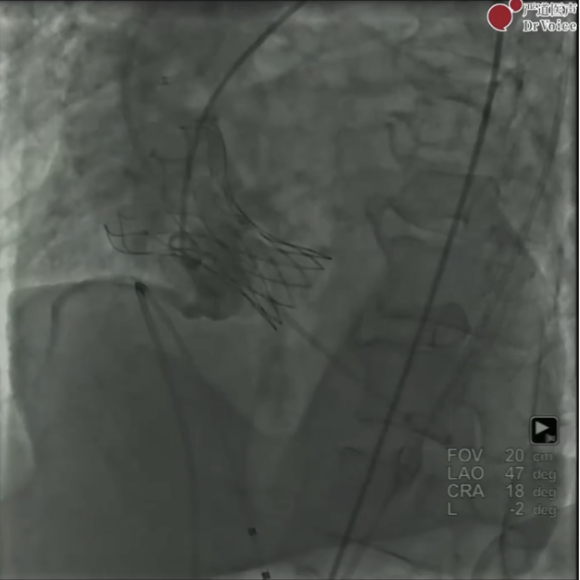

手术经右股动脉入路,首先使用24mm球囊预扩张,可见主动脉瓣反流并未加重。

对左右冠进行造影发现不显影,洪浪教授凭借经验反复调整导管位置,寻找LCA及RCA开口位置。

随后在snare辅助下,送入瓣膜,定位完成后在起搏状态下释放。

手术结果

复查造影LCA及RCA血流未受到影响,超声提示中度瓣周漏。考虑到患者术前即存在中度主动脉瓣关闭不全,且血流动力学参数目前相对满意,造影显示瓣膜锚定位置良好,术者及与会专家一致决定不再进行球囊后扩张,防止因球囊扩张造成RCA阻塞。